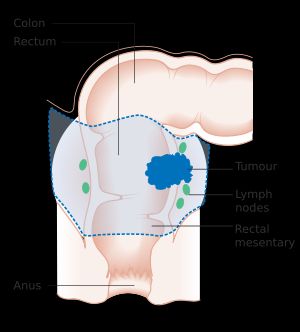

대장암 진단은 대장 내시경이나 S상 결장 내시경을 통해 종양이 의심되는 부위를 채취하여 이루어진다.[369] 이후 조직 샘플을 현미경으로 검사하여 확진한다.[369] CT 스캔에서 처음 발견되기도 한다.[370]

전이 여부는 흉부, 복부 및 골반의 CT 스캔을 통해 확인한다.[369] 경우에 따라 PET 및 MRI과 같은 다른 영상 검사를 시행할 수 있다.[369] MRI는 종양의 국소 병기를 결정하고 최적의 수술 방법을 계획하는 데 특히 유용하다.[370]

생검 또는 수술로 채취한 조직을 분석하여 종양의 조직병리학적 특성을 확인한다. 병리 보고서에는 종양 세포의 현미경적 특성, 종양이 건강한 조직으로 침투하는 양상, 종양의 완전 제거 여부 등이 기술된다. 대장암의 가장 흔한 형태는 선암종으로, 전체 대장암의 95%[84]에서 98%[85]를 차지한다. 드물게 림프종, 선편평세포암, 편평 세포 암종 등이 발생할 수 있으며, 일부 아형은 더 공격적이다.[86] 불확실한 경우에는 면역조직화학 검사를 시행할 수 있다.[87]

5. 2. 병기 결정

암의 병기는 영상의학적 소견과 병리학적 소견을 모두 기반으로 한다. 대부분의 다른 형태의 암과 마찬가지로 종양 병기는 초기 종양이 얼마나 퍼졌는지, 림프절 및 더 먼 장기에 전이가 있는지 고려하는 TNM 시스템을 기반으로 한다.[20]대장암의 병기 분류는 주로 국소 침윤의 정도, 림프절 침윤의 정도 또는 원격 전이 유무에 따라 결정된다. 국제적으로는 '''TNM 분류'''가 병기 분류에 사용된다.